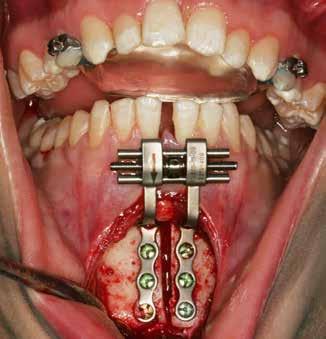

INDRE VÆKSTFORSTYRRELSER I DEN DENTOALVEOLÆRE OG BASALE KÆBERELATION kan almindeligvis kompenseres og korrigeres ved ortodonti og/eller vækstadapterende behandling (1). Imidlertid nødvendiggør ekstreme vækstforstyrrelser i den dentoalveolære og basale kæberelation oftest ortodontisk-kirurgisk behandling involverende forudgående ortodontisk nivellering af tandbuerne og efterfølgende kirurgisk korrektion af de basale kæberelationer ved en Le Fort I-osteotomi og/eller bilateral sagittal splitosteotomi (BSSO) (2). Manglende korrektiv behandling af vækstforstyrrelser i den dentoalveolære og basale kæberelation kan medføre tygge- og bidfunktionelle gener, malokklusion, tvangsføring af mandiblen, trangstilling, psykosociale problemer og uhensigtsmæssigt slid af tænderne (3). Sundhedsstyrelsens specialevejledning har derfor opstillet vejledende kriterier for tilbuddet om kirurgisk korrektion af medfødte og erhvervede kæbeanomalier, når vækstforstyrrelserne i den dentoalveolære og basale kæberelation ikke kan korrigeres ved konventionel ortodontisk behandling alene (4). Disse visitationsretningslinjer kan findes på Dansk Selskab for Oral og Maksillofacial Kirurgis og Foreningen af Specialtandlæger i Ortodontis hjemmesider.

Fig. 1. Klinisk undersøgelse visende et stort horisontalt maksillært overbid kombineret med et dybt bid og bilateralt saksbid på molarerne og præmolarerne.

Fig. 1. Clinical examination revealed a large horizontal maxillary overbite combined with a deep bite and bilateral scissor bite on the molars and premolars.

Betragtelige transverselle okklusionsafvigelser i maksillen behandles almindeligvis med vækstadapterende ortodontisk behandling før begyndelse af vækstspurten, mens kirurgisk korrektion ved en sektioneret Le Fort I-osteotomi eller kirurgisk assisteret ganeekspansion oftest er nødvendig efter afsluttet vækst (3). Transverselle okklusionsafvigelser i mandiblen kan ikke korrigeres ved vækstadapterende ortodontisk behandling som følge af afsluttet vækst i sutura symphysis menti før etårsalderen, hvorfor betragtelige transverselle okklusionsafvigelser oftest korrigeres ved en udvidelse eller komprimering af maksillen (5). Imidlertid er kirurgisk korrektion af betragtelige transverselle okklusionsafvigelser ved en sektioneret Le Fort Iosteotomi eller kirurgisk assisteret ganeekspansion forbundet med stor tendens til recidiv (3), hvorfor transversel udvidelse af mandiblen kan være nødvendig for at mindske recidivtendensen.

Betragtelige transverselle okklusionsafvigelser i den underudviklede mandibel kendetegnes ved en V-formet tandbue, unieller bilateralt saksbid, oral inklinering af molarerne og præmolarerne samt trangstilling i underkæbefronten (6). Mindre transverselle okklusionsafvigelser i mandiblen kan oftest korrigeres ved hjælp af ortodonti alene, mens større transverselle okklusionsafvigelser eventuelt i kombination med andre vækstforstyrrelser i den dentoalveolære og basale kæberelation oftest behandles ved kirurgisk korrektion involverende mandibulær midtlinjeosteotomi eller mandibulær midtlinjedistraktionsosteogenese (MMDO) (6).

Mandibulær midtlinjeosteotomi anvendes almindeligvis ved moderate transverselle okklusionsafvigelser og kan eventuelt kombineres med en bilateral sagittal splitosteotomi, mens mandibulær midtlinjedistraktionsosteogenese udelukkende anvendes ved ekstreme transverselle okklusionsafvigelser og ikke kan kombineres med andre osteotomier på mandiblen.

I nærværende artikel præsenteres et usædvanligt patienttilfælde med en betragtelig transversel okklusionsafvigelse i mandiblen, som blev korrigeret ved ortodonti og mandibulær

Fig. 2. A-C. Panorama, profilrøntgen og CBCT-optagelse viser overensstemmelse med de kliniske fund visende et stort horisontalt maksillært overbid og bilateralt saksbid i sideregionerne.

Fig. 2. A-C. Panoramic x-ray, profile x-ray, and CBCT-image show agreement with the clinical findings showing a large horizontal maxillary overbite and bilateral scissor bite in the lateral regions.

midtlinjedistraktionsosteogenese, og de forskellige distraktionsapparaturer til korrektion af transverselle okklusionsafvigelser i mandiblen diskuteres.

Fig. 3. A. Gennemgående midtlinjeosteotomi svarende til regio 1-1. B. Distraktionsapparatur monteret og fikseret på hver side af osteotomien. C. Panoramaoptagelse under distraktionsfasen. D. Panoramaoptagelser efter distraktionsfasen er afsluttet. E. Intraoperativt klinisk foto efter fjernelse af distraktionsapparaturet, hvor der ses knogledannelse svarende til den tidligere knoglespalte.